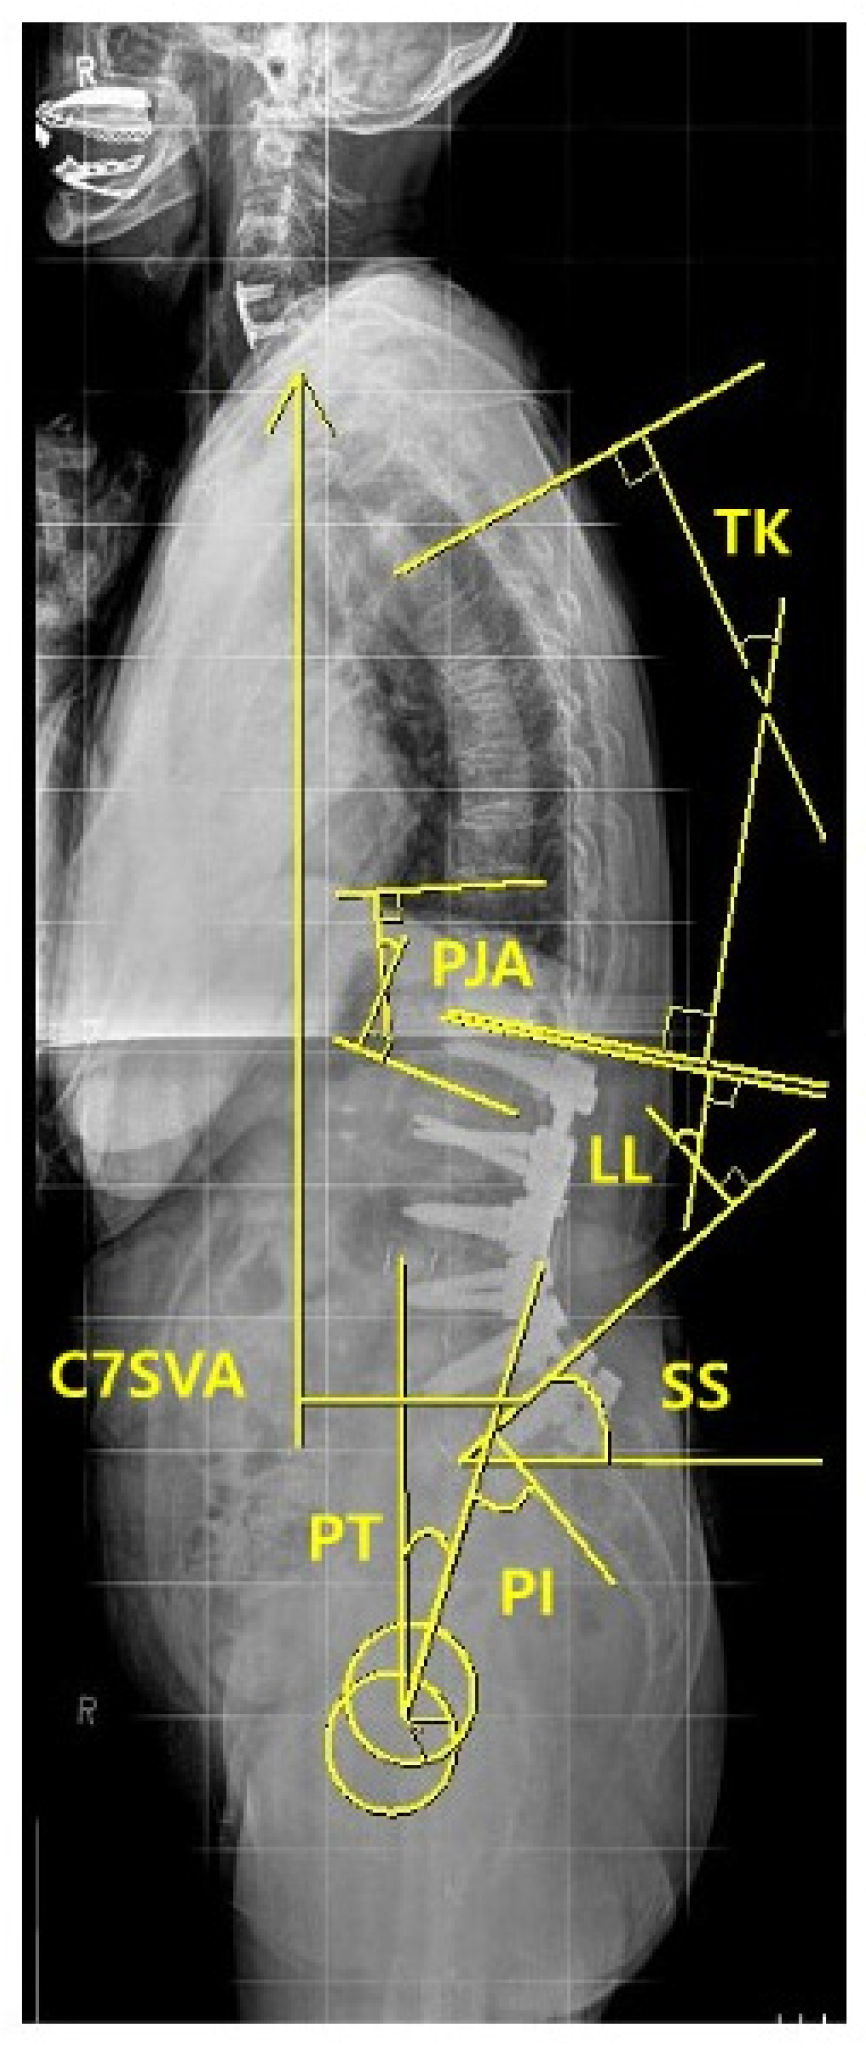

| Risk Factors | PJK Group (n = 23) | Non-PJK Group (n = 33) | p |

|---|---|---|---|

| Preoperative Parameters | |||

| TK (°), mean ± SD | 7.6 ± 14.3 | 13.9 ± 12.7 | 0.153 |

| TLK (°), mean ± SD | 0.75 ± 0.9 | 0.67 ± 1.0 | 0.082 |

| PJA (°), mean ± SD | 2.98 ± 8.0 | 1.99 ± 12.2 | 0.583 |

| LL (°), mean ± SD | 7.2 ± 24.7 | 20.2 ± 24.5 | 0.115 |

| SS (°), mean ± SD | 23.0 ± 8.5 | 30.1 ± 12.3 | 0.057 |

| PT (°), mean ± SD | 34.0 ± 7.2 | 25.8 ± 13.0 | 0.032 * |

| PI (°), mean ± SD | 56.9 ± 7.0 | 55.5 ± 10.9 | 0.663 |

| C7 SVA (mm), mean ± SD | 92.0 ± 48.5 | 85.1 ± 43.4 | 0.720 |

| Immediate (3 months) postoperative parameters | |||

| TK (°), mean ± SD | 20.7 ± 8.4 | 19.9 ± 17.3 | 0.876 |

| TLK (°), mean ± SD | 23.5 ± 9.9 | 8.7 ± 12.2 | <0.001 * |

| PJA (°), mean ± SD | 20.9 ± 7.7 | 10.7 ± 8.1 | <0.001 * |

| LL (°), mean ± SD | 43.8 ± 13.5 | 45.9 ± 9.4 | 0.569 |

| SS (°), mean ± SD | 32.0 ± 9.4 | 35.6 ± 8.1 | 0.215 |

| PT (°), mean ± SD | 24.1 ± 11.2 | 18.7 ± 8.6 | 0.092 |

| PI (°), mean ± SD | 55.8 ± 7.4 | 53.7 ± 7.0 | 0.376 |

| C7 SVA (mm), mean ± SD | 49.9 ± 38.9 | 37.3 ± 35.6 | 0.303 |